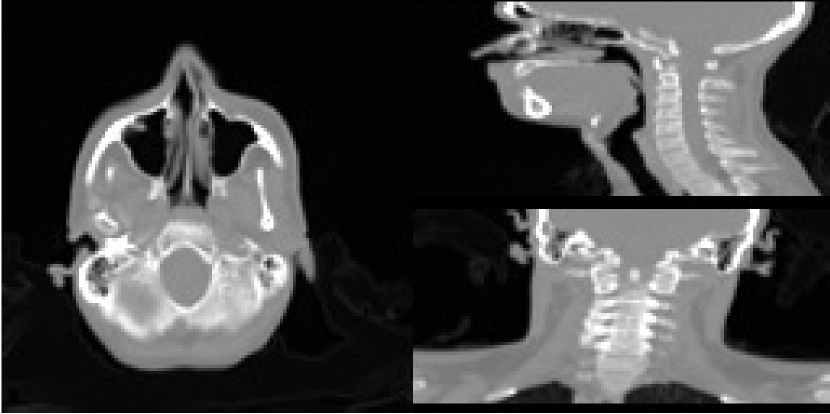

The data set we are using is derived from repeat CT scans of a neck cancer patient from the Cancer Image Archive [17][18]. With these, we will use the first CT scan as the planning image, then synthesise CBCT measurements on the follow up after 5 months—these are shown in Figures 3(a) and 3(b) respectively. A strong advantage of using this approach is that one has access to a ground truth, against which one can perform valid quantitative assessments.

To generate the CBCT data, we used the Monte-Carlo simulation tool Gate [19] with a 60 keV monoenergetic source on the oracle image, where we did runs with and photons over 160 projection angles to represent two levels of dose.